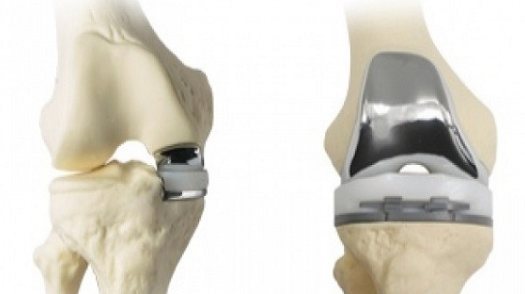

무릎 치환술(Total Knee Arthroplasty)

적응증: 무릎 치환술은 심각한 무릎 관절염, 류마티스 관절염, 골관절염 또는 무릎 부상으로 고통받는 개인에게 권장되는 경우가 많습니다.

절차: 이 수술에서는 허벅지 뼈(대퇴골)와 정강이뼈(경골)의 끝 부분을 포함하여 무릎 관절의 손상된 부분을 금속 및 플라스틱 부품으로 교체합니다. 이러한 구성 요소는 관절의 자연스러운 움직임과 기능을 재현합니다.

혜택: 무릎 치환술은 통증을 크게 줄이고 이동성을 향상시키며 환자의 일상 활동 수행 능력을 향상시킬 수 있습니다.